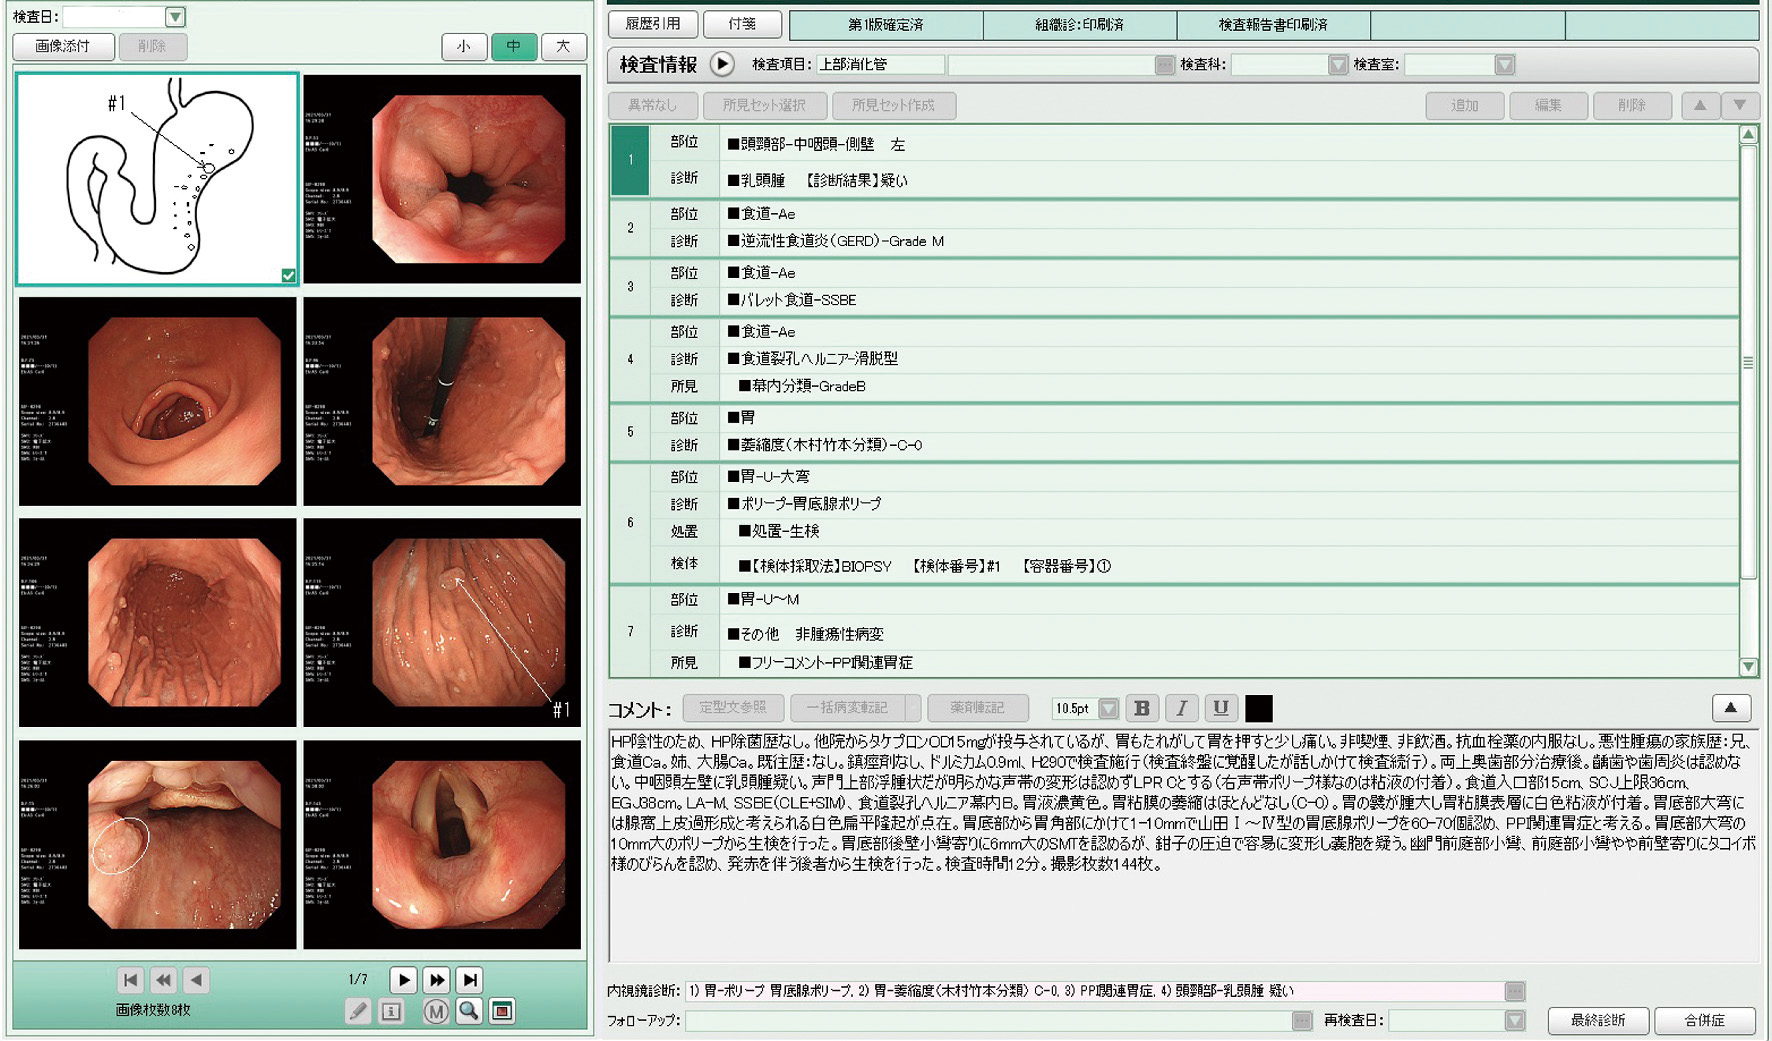

【症例2】60歳代,女性.

主訴:胃もたれ,圧迫時の胃痛

既往歴など:H. pyloriの除菌歴なし.非喫煙,非飲酒.

悪性腫瘍の家族歴:兄,食道癌.姉,大腸癌.

内服歴:ランソプラゾール15mg/日

内視鏡検査法:鎮痙剤なし,鎮静剤:ミダゾラム0.9 mL,炭酸ガス送気使用,経口挿入.IEE (NBI) 併用.

使用機種:GIF–H290 (オリンパス,面順次方式電子内視鏡)

検査場所:増山胃腸科クリニック (大田原市,増山仁徳院長)

内視鏡画像:ⓔ動画11-1-5 (144枚の静止画を連続再生)

内視鏡検査所見・診断:report (図2) 参照

検査時間:12分

撮影枚数:144枚

生検結果:Group 1 fundic gland polyp